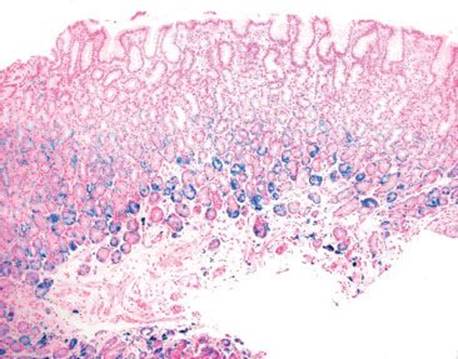

Figure 2.236 Iron pattern C/“gastric glandular siderosis” (Prussian blue). The iron is highlighted by the Prussian blue stain. In this pattern, the characteristic deposits are uniform and generally restricted to the deep gastric glands and occasional deep stromal cells.

Gastric iron deposition is seen in up to 3.8% of upper tract biopsies (Fig. 2.228).23,24,183–185 In a study of 500 gastric biopsies, the deposition was demonstrated in three generalized patterns. Pattern A (also referred to as “nonspecific gastric siderosis”) was the most common subpattern and involved 2.2% of specimens (Figs. 2.229 and 2.230). This subpattern was associated with prior mucosal microhemorrhages, and the subtle depositions were predominantly identified within macrophages and stromal cells of the lamina propria. Pattern B (also referred to as “iron pill gastritis”) was seen in 0.8% of the biopsies and was consistently associated with ferrous sulfate therapy. This deposition was coarse and crystalline and predominantly identified in the extracellular and most superficial aspect of the biopsy (Figs. 2.231–2.234). In this subpattern, the background mucosa had a reactive gastritis/gastropathy pattern with erosions, ulcerations, and fibrino-inflammatory exudate common. In a separate study of 1,300 gastric biopsies, a similar “iron pill gastritis” injury pattern was detailed.184 This latter group reproduced the identical iron deposits in the laboratory by oxidizing ferrous sulfate tablets, providing clear evidence for the iron origin of these deposits. The mechanism of injury is a bit unclear in this subpattern. Some speculate that the iron pill has a direct caustic effect on the adjacent mucosa, whereas others suggest that the iron deposits may simply colonize previously injured mucosa. Pattern C (also referred to as “gastric glandular siderosis”) was the least common pattern, involving 0.6% of the specimens. This subpattern was associated with iron overload settings, such as hereditary hemochromatosis and multiple blood transfusions. The characteristic deposits were subtle, uniform, and identified in the deep antral and oxyntic glands (Figs. 2.235–2.239). The iron deposits can be highlighted blue with a Prussian blue iron special stain. Recognition is important to help prevent further injury and potential stricture formation (pattern B), to suggest pertinent iron overload evaluation (pattern C), and to avoid overdiagnosing the marked reactive epithelial change as dysplasia.

• Pattern C/“gastric glandular siderosis” is associated with iron overload; the deposits are subtle, uniform, and identified in the deep antral and oxyntic glands.